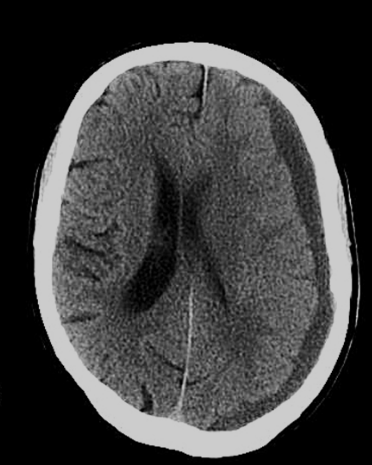

왼쪽 뒷 머리속에 피가 고여 있는데, 쉽게 머리라서 어떻게 피를 제거할 수가없다고 하시더라구요...